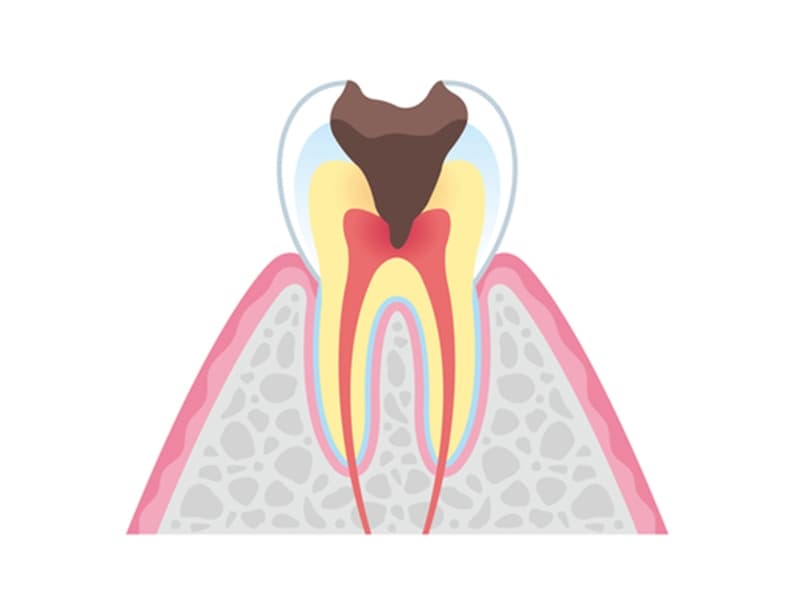

- C3

神経まで侵されたむし歯

むし歯が歯髄まで到達すると、激しい痛みを伴うのが特徴です。この段階では、感染した歯髄を除去し、根管治療を行う必要があります。根管内の感染組織を徹底的に除去・洗浄した後、特殊な材料で根管を封鎖。適切な修復物を装着して治療は完了します。